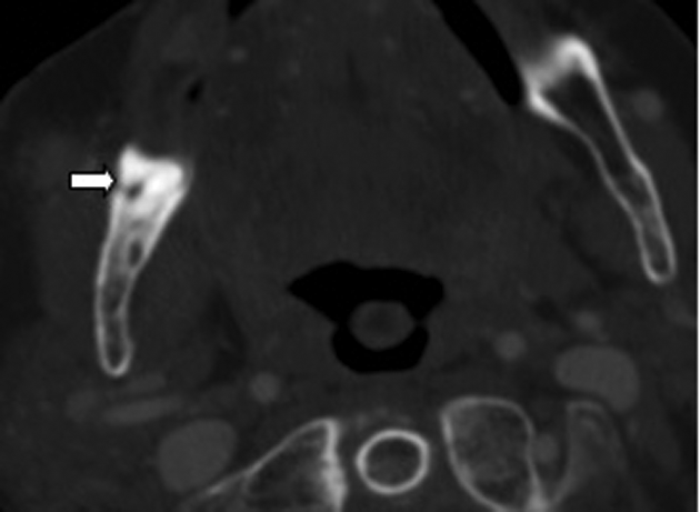

Clinical examination excluded a dental cause, as the patient was edentulous, however an ultrasound demonstrated an abscess over the right masseter muscle. Figure 3 shows an abscess collection in the right buccal space. Figure 4 demonstrates the cause of the abscess (and otalgia) - a tooth root buried underneath the gingiva, with associated buccal bone perforation.

Figure 4: Bone window axial CT demonstrating a retained root (white arrow).